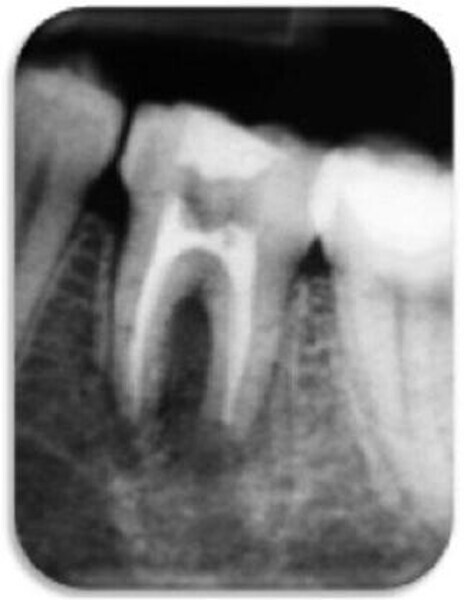

Leczenie endodontyczne autogennego przeszczepu zęba